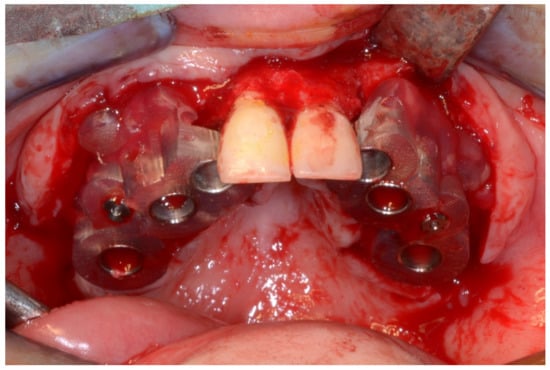

6.2.4. Intra-Operative Documentation:

In March 2013, twelve guided dental implants were placed at sites # 12, # 13, # 15, # 22, # 23, # 25, # 33, # 34, # 36, # 43, # 44, and # 46 (Figure 22, Figure 23, Figure 24, Figure 25 and Figure 26)

Figure 22.

Maxillary surgical drilling guides temporarily supported and fixed with mini-screws.

Figure 23.

Mandibular surgical drilling guides temporarily supported and fixed with mini-screws.

Figure 24.

Implant bed preparation using guided drills inserted into specific ad hoc drill handles.

Figure 25.

Guided implant insertion.

Figure 26.

Mandibular implants in place.